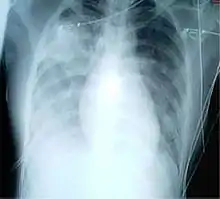

A chest x-ray of a patient with severe viral pneumonia due to SARS